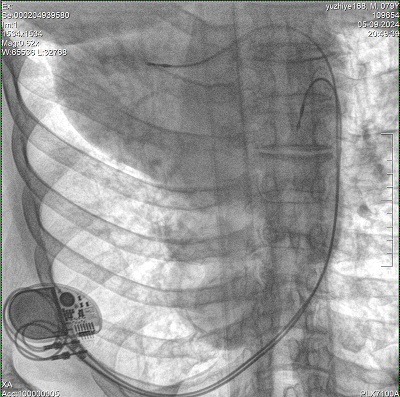

具備血管造影及數(shù)字減影(DSA)、路徑圖(Road-map)、透視、攝影等功能。 廣泛適用于介入科、血管外科、腫瘤科、消化內(nèi)科及骨科等多個(gè)臨床科室,典型應(yīng)用包括:TACE(肝腫瘤栓塞與化療灌注術(shù))、心臟起搏器置入術(shù)、四肢動(dòng)脈造影術(shù)、下肢靜脈濾器置入術(shù)、ERCP(經(jīng)內(nèi)鏡逆行胰膽管造影術(shù))等。

設(shè)備搭載自主研發(fā)的大功率高壓發(fā)生器、高熱容球管與大尺寸平板探測器,配合先進(jìn)圖像處理算法及高效冷卻循環(huán)系統(tǒng),能夠在長時(shí)間手術(shù)過程中持續(xù)輸出高清圖像并保持幀率穩(wěn)定。

預(yù)留高壓注射器聯(lián)動(dòng)接口,C形臂開始透視時(shí),高壓注射器自動(dòng)注入造影劑,提高術(shù)中造影減影效率,減少醫(yī)師手推造影劑所受到的輻射暴露劑量。